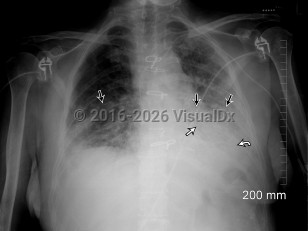

InfluenzaInfluenza